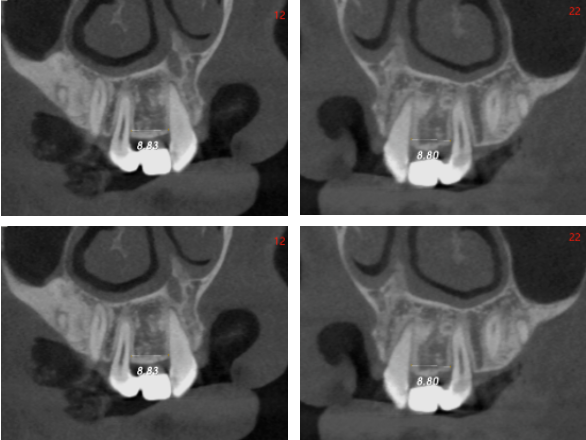

影像学检查

●骨宽度稍欠,骨宽度约4.0mm,骨高度约15mm

●邻牙未见明显异常